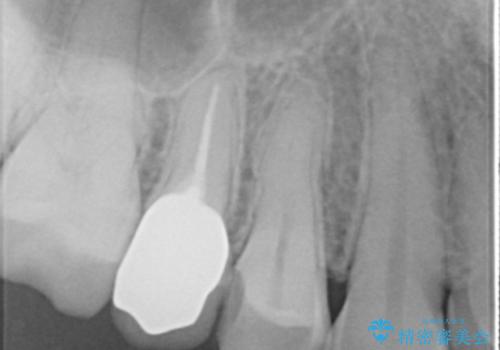

患者様の天然歯はグラデーションがあり切縁(歯冠の先端)はやや透けていて透明感があるのに対し、前歯(右上1)の差し歯はやや黄色く不透明で単調な色味でした。

患者様のご希望により、右上1はジルコニアクラウン(スペシャル)、右上5はジルコニアクラウン(スタンダード)へやりかえることにしました。

再根管治療に関しては、患者様がご希望されず症状もないため行っておりません。

ご予算の都合とご希望により、右上5の土台はやりかえずに元の土台のまま治療を進めました。